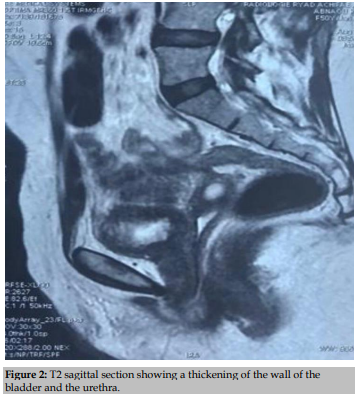

Magnetic resonance imaging (MRI), performed in August 2018, revealed a regular and significant non-tumoral thickening of the urethral walls over 20 mm, its walls are in T1 isosignal and T2 hypersignal with regular thickening. bladder walls and a collapsed vaginal cavity (Fig. 2).